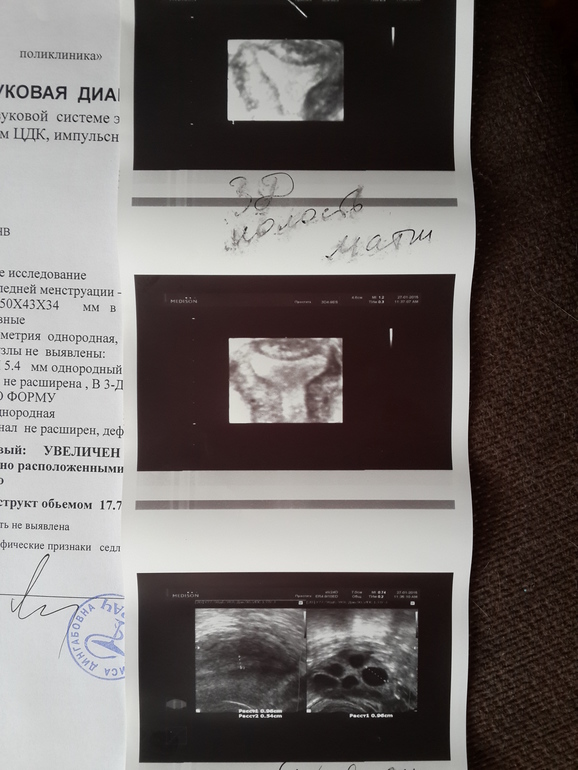

здесь аппарат получше, надеялась, что рассмотрят ЖТ, но нет, чуда не случилось... овуляции не было, да еще и матка у меня седловидная, оказывается... все надежды, которые я возлагала на этот цикл, рухнули... я разбита, вчера у меня случилась истерика, сегодняшнее узи меня добило окончательно... я устала... на следующий цикл хотела на стимуляцию идти, но уже ничего не хочется, только плакать...

мне Ли рассказала и показала все, даже в базе показала фотки нормальной и двурогой матки, чтоб я убедилась, что у меня седловидная, мне прям интересно с ней было.

да знаю, что отзывы о поликлинике не очень, но я сама все видела, так она измеряла и т.д., так что ошибки тут не должно быть, я сама за всеми измерениями наблюдала.

У вас спкя? Яичники довольно большие. Какой уровень лг/фсг? Просто для стимуляции необходимо, чтобы они были не сильно увеличены

да,у меня СПКЯ. я гормоны сдавала последний раз ровно год назад , тогда был ЛГ 5.05, а ФСГ 5.46